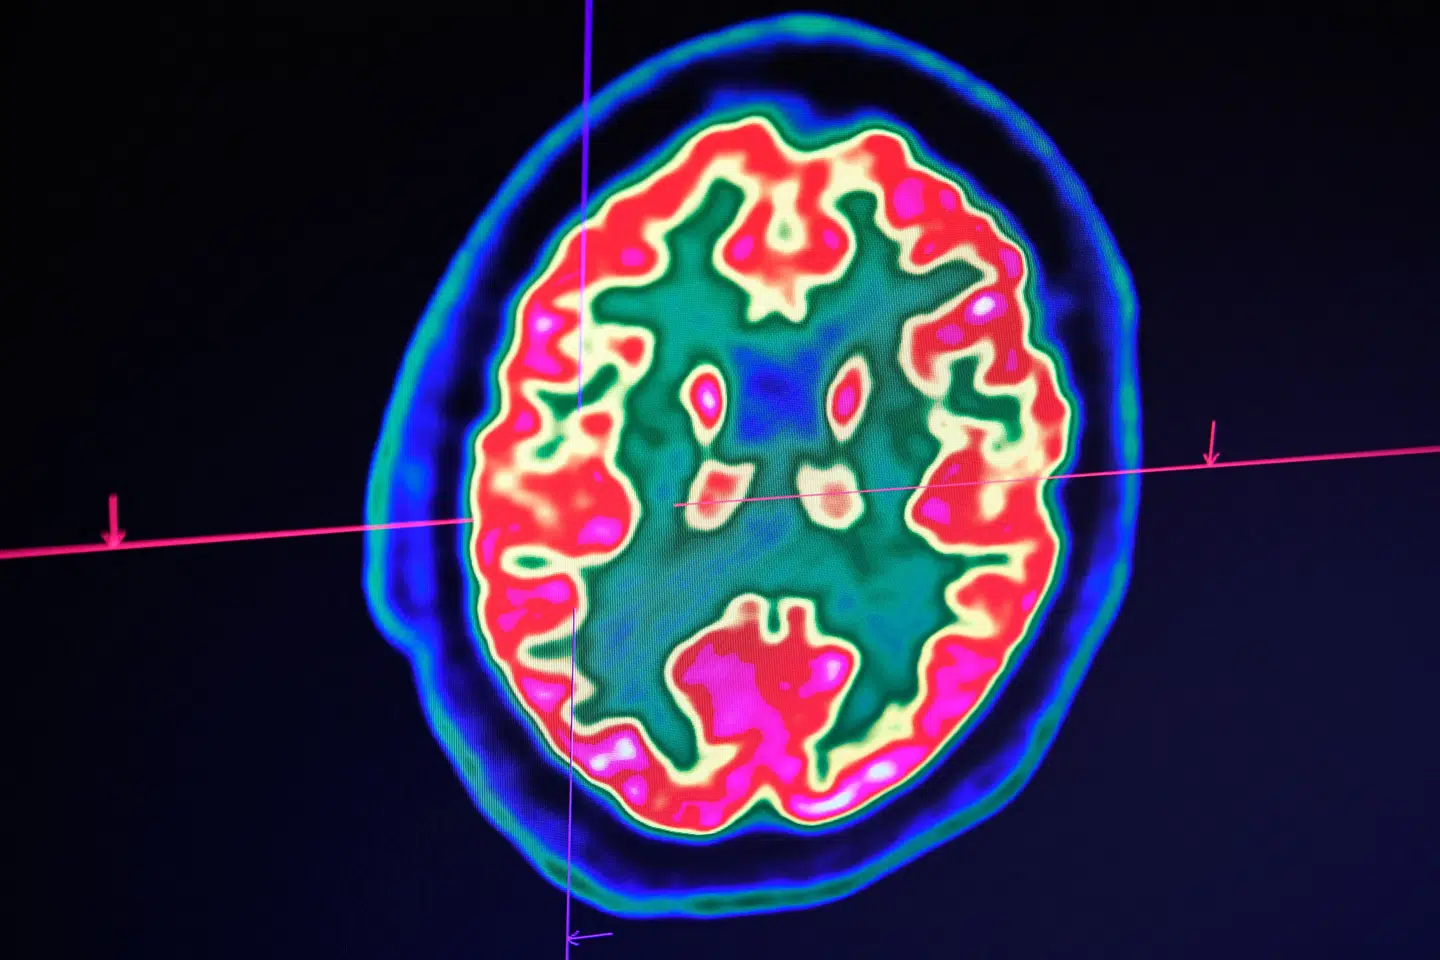

Professorerne har identificeret de mekanismer, der omdanner berøring, vibration eller tryk på huden til nerveimpulser.

De har også kortlagt, hvordan disse signaler overføres til rygmarven, hvor de bearbejdes, før de fortsætter til hjernen.

Her skabes vores oplevelse af berøring og smerte og de følelsesmæssige og adfærdsmæssige reaktioner, der følger med, når vi interagerer med den fysiske verden, lyder det videre.